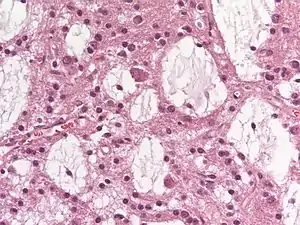

Dysembryoplastic neuroepithelial tumours are largely glioneuronal tumours, meaning they are composed of both glial cells and neurons.[2]

Three subunits of DNTs have been commonly identified:[2]

- Simple: Specific glioneuronal elements are the sole components of simple DNTs.[2]

- Complex: Glial nodules and/or type 3b focal cortical dysplasia (FCD), in addition to the glioneuronal elements are present in complex DNTs.[4] Both the nodules and FCD can be present within the same tumour, though only 47% of complex DNTs are linked to FCD.[2]

- Nonspecific: Nonspecific DNTs are lacking the glioneuronal elements common to DNTs but will show glial nodules and/or type 3b FCD.[2] Eighty-five percent of nonspecific case of DNTs show this FCD.[2]

There currently exists some debate over where to make the proper division for the subunits of DNTs. A fourth subunit is sometimes noted as a mixed subunit. This mixed subunit expresses the glial nodules and components of ganglioglioma.[1] Other findings suggest that DNTs require a reclassification to associate them with oligodendrogliomas, tumours that arise from solely glial cells.[3] These reports suggest that the neurons found within DNTs are much rarer than previously reported. For the neurons that are seen in the tumours, it is suggested that they had been trapped within the tumor upon formation, and are not a part of the tumour itself.[3]